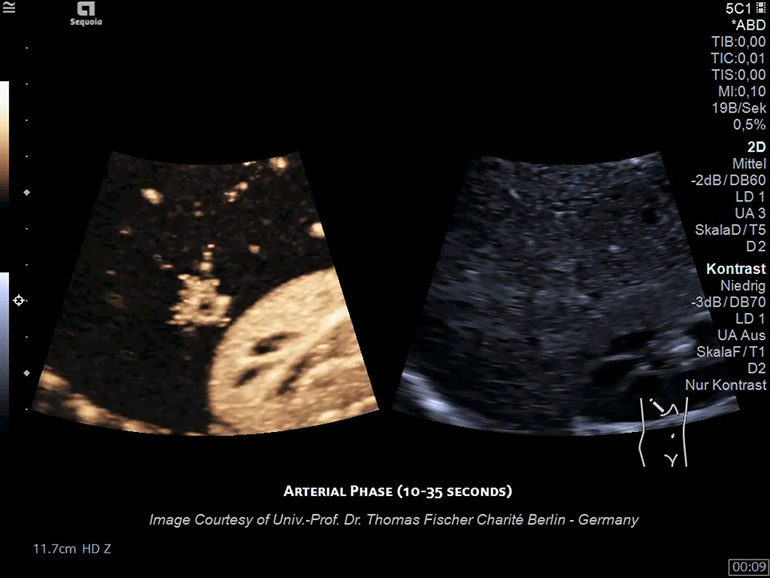

УЗИ с контрастным усилением (CEUS)

Мощная архитектура УЗ-системы ACUSON Sequoia обеспечивает визуализацию контрастного препарата на больших глубинах и с большей четкостью, чем когда-либо ранее.

Технология импульсных последовательностей для режима контрастирования (CPS) Технология импульсных последовательностей контрастирования обеспечивает подавление артефактов яркости при движении потока крови и превосходное подавление сигнала от смещающихся тканей, участвующих в акте дыхания. Благодаря своей высокой специфичности и чувствительности технология CPS позволяет получать изображения на большей глубине у тех пациентов, для которых ранее контрастные исследования затруднены.

​Контрастная гармоническая визуализация (CHI) Режим контрастной гармонической визуализации обеспечивает высокое разрешение и высокую частоту кадров с одновременным сохранением долговечности микропузырьков (по сравнению с CPS) контрастного препарата. Режим CHI — отличный инструмент для визуализации кровоснабжения поверхностных структур, который при необходимости обеспечивает и превосходную глубину проникновения ЭХО-сигнала.